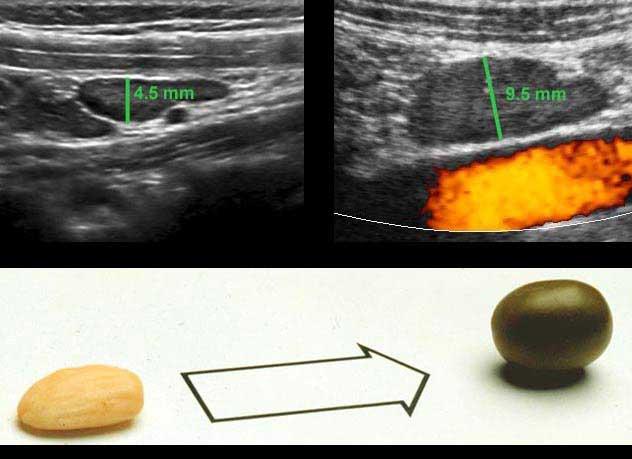

Đường kính ngoài của ruột thừa được đo theo cách tương tự như ruột: trong quá trình ép vừa phải từ bờ ngoài của lớp cơ thành bụng trước đến bờ ngoài của lớp cơ thành bụng sau.

Được đo như vậy, đường kính của ruột thừa bình thường này (trái) là 4,5 mm và của ruột thừa viêm này (phải) là 8,5 mm.

Trong nhiều sách giáo khoa, giá trị ngưỡng cắt được báo cáo là 6 mm, tuy nhiên đây không phải là giá trị đáng tin cậy.

Rettenbacher (Radiology 2001; 218: 757-62) đã thực hiện một nghiên cứu lớn và phát hiện rằng đường kính của ruột thừa bình thường từ 6 mm trở lên chiếm 27% các trường hợp, với khoảng dao động từ 2-13 mm.

Đo lường trên CT đánh giá cao hơn đường kính ruột thừa so với siêu âm.

Trong y văn, đường kính trung bình trên CT của ruột thừa bình thường là 6,5-8 mm (dao động từ 3 đến 14 mm).

Tài liệu y văn chỉ ra rằng đường kính siêu âm của ruột thừa bình thường là 6 mm hoặc nhỏ hơn trong 73% các trường hợp.

Đây là hình ảnh ruột thừa bình thường khi bị ép trong mười bệnh nhân khác nhau với đường kính AP dao động từ 2-10 mm (Lưu ý cùng một thang đo cm).